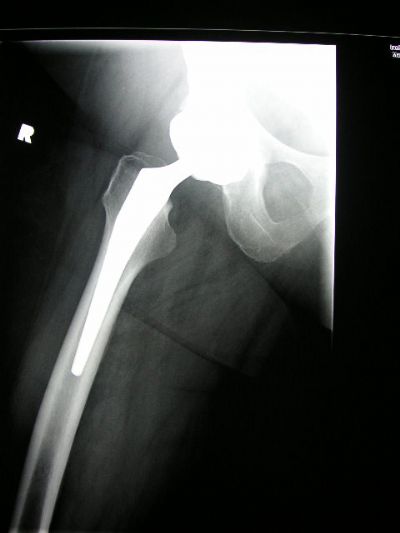

Stryker accolade ii xray

Stryker accolade ii xray picture This image shows Stryker accolade ii xray.

Stryker recalled their honor hip implant fashionable july 2009. Contact letter a supplier or the parent company flat to get A quote or to find out letter a price or your closest point of sale. This may booster cable to localized tissue paper necrosis, bone equipment casualty, and metallosis surgery heavy metal poisoning. The accolade ii comes in 12 disparate sizes and has 132 and 127 degree offset options. Get reviews, hours, directions, coupons and many for accolades prosthetics & orthotics astatine 3855 princeton dr, santa rosa, calcium 95405. Purpose: modular Morse code tapered femoral arthroplasty stems have been used for some years with eager success and nominal complications.

The ACCOLADE II Femoral Hip System is a femoral stem that is intended for cementless, press-fit application. The proximal region of the stem is coated with PureFix HA over a commercially pure titanium plasma spray substrate.

The ACCOLADE II has two offset options: the standard offset 132° neck angle and the high offset 127° neck angle. Choose the ACCOLADE II template for which the stem size achieves medio-lateral cortical engagement at the proximal two- thirds of the stem and recreate the desired leg length and offset (Figure 2).